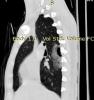

На представленных СК-томограммах на электронном носителе органов грудной полости пациента А №4473 от 23.09.20254 года, №4478 от 24.09.20254 года, №4511 от 28.09.20254 года - визуализируется перелом средней трети левой ключицы по типу «зеленой веточки», без смещения отломков, без признаков консолидации. В грудине дифференцируются зоны роста. Данных за перелом грудины, ребер, грудных позвонков не выявлено. Легкие по всем полям с обеих сторон прилежат к грудной клетке. Данных за пневмоторакс не выявлено. Бронхо-сосудистый рисунок несколько усилен. В задне-медианных отделах S6 правого легкого, на уровне тел позвонков Th5-Th8, на фоне обширной зоны контузии легкого примерным размером до 58х52х20 мм визуализируются две воздушные полости неправильной овальной формы, размером до 26х14х6 мм и до 12х10х3 мм. Полости с небольшими уровнями гетерогенного жидкостного содержимого (кровь). В правом легком: в прикорневой зоне, в S8, S9 визуализируется до 5 очагов контузии легкого по типу «матового стекла» размером от 12х10 мм до 20х15 мм. В левом легком: в S1\S2, в S4 визуализируются до 3 очагов контузии легкого по типу «матового стекла» размером от 11х10 мм до 14х9 мм. Диафрагма обычно расположена. В полости перикарда и в плевральных полостях свободной жидкости не выявлено. Заключение: КТ-картина участков разрыва правого легкого в задне-медианных отделах S6; разнокалиберных зон ушиба в обоих легких. Перелом с\3 левой ключицы без смещения. Травматические изменения могут соответствовать сроку травмы в ДТП от 23.09.2025 года

Картинки от рентгенолога